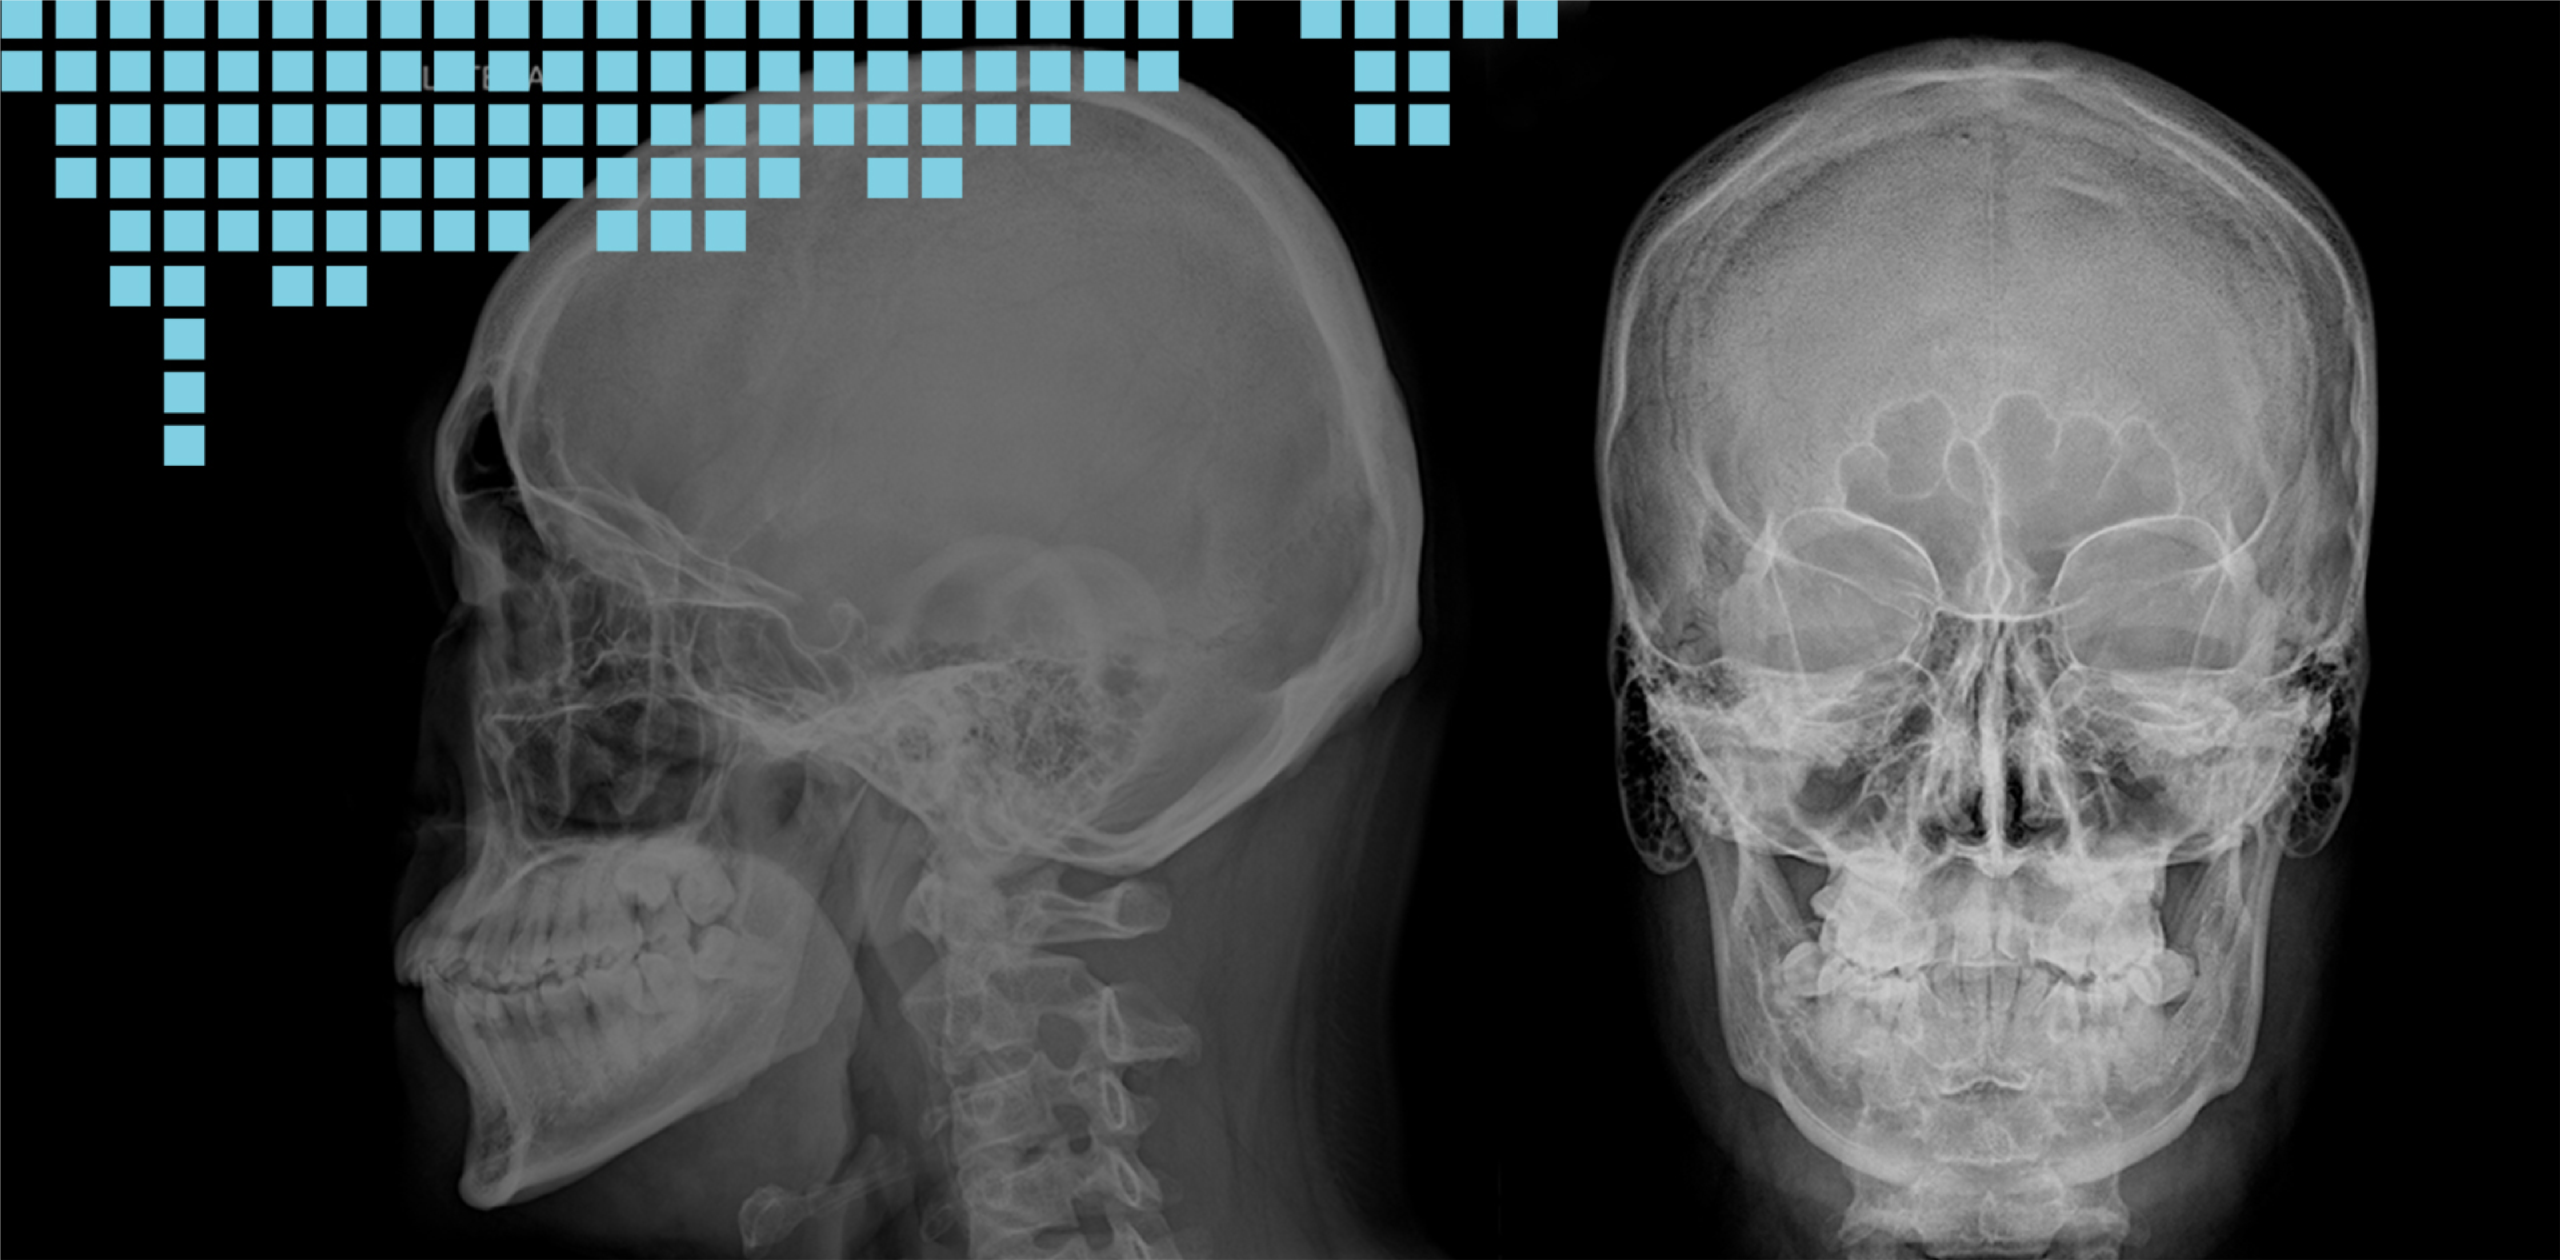

Our advanced digital radiography systems enhance productivity, patient comfort and workflow. Images produced can be transferred digitally throughout the hospital via network to improve patients’ turnaround time and throughput.

• Chest X-Ray

• Skull X-Ray